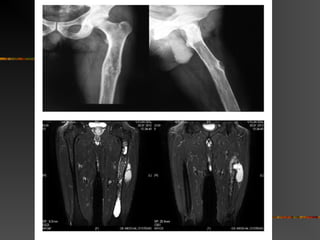

Orthopedics

 50 yr – pain & swelling – Lt – thigh

 Needle biopsy – 6 yrs back

 HPE – HC – Lt femur

 Surg – adv – pt – refused / Trt – cons.

 L/E Lge immobile / painless mass – AL surf

lt.thigh & limping with pain

 Lab – WNL / U/S – abd & CT – thorax - N

 Plain X-ray & MRI – HC